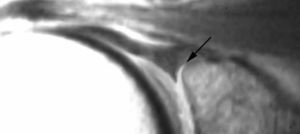

Lesión de Perthes

La lesión de Perthes es similar a la de Bankart, con la excepción de que no existe rotura capsuloperióstica, aunque el periostio puede estar separado del borde anterior del margen glenoideo (fig. 10). Esta lesión puede ser difícil de visualizar, incluso con artrorresonancia, a menos que se obtengan imágenes con la posición de abducción y rotación externa (ABER). En un estudio de 10 casos, verificados quirúrgicamente, Wisher et al17 comprobaron que el 50% de las lesiones de Perthes sólo podían visualizarse en la posición de ABER.

Fig. 10.--Lesión de Perthes. Artrorresonancia T1 con saturación grasa en posición ABER (abducción y rotación externa), donde se observa un arrancamiento parcial del labio glenoideo (flecha) con conservación de la unión capsuloperióstica.